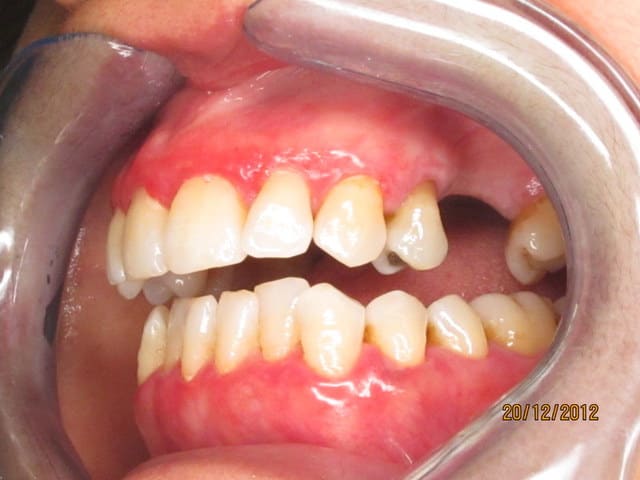

Je viens de voir cette patiente, qui consulte pour le problème esthétique lié à la couleur très gênante de sa gencive.

Cette patiente, originaire d’Afrique du nord a la trentaine, pas de pathologie générale connue, pas d'allergie.

elle a été traitée il y a 2 mois par surfaçage et motivation aux soins locaux qu'elle applique plutôt sérieusement.

Au sondage pas de poche, quasiment pas de saignement.

La couleur rouge s'estompe à la pression, on sent la gencive très fine et lisse.

Aucune douleurs.

Ca me rappel le cas d'une patiente qui avait une penphigoîde, qu'en pensez vous ? On voit sur les photos des trace qui pourrait laisser penser à des desquamations de bulles.